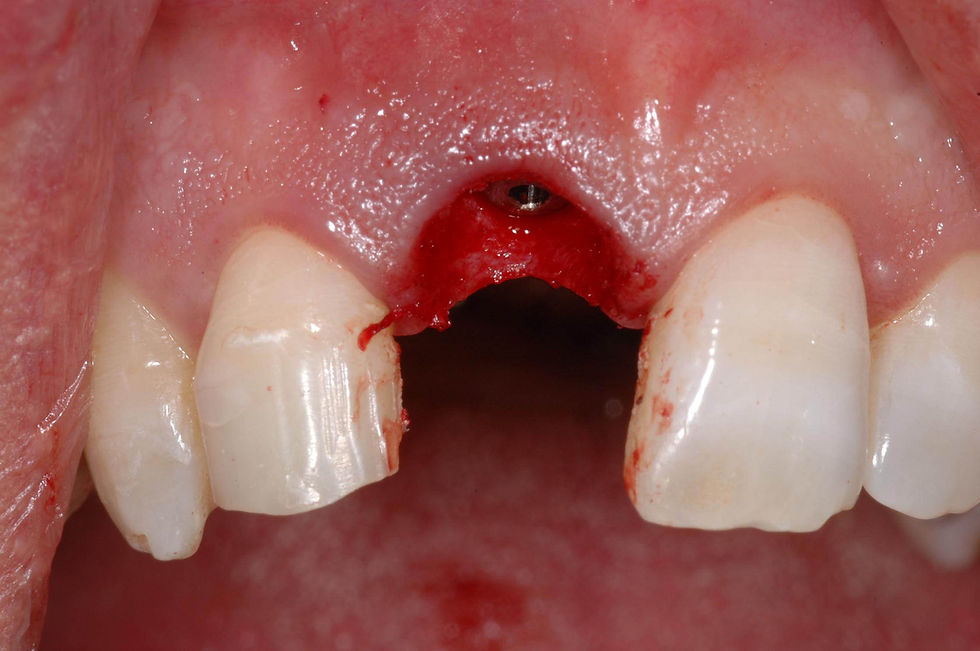

After having verified the correct preparation of the implant site in the three planes of the space, a Prama RF 4.25x13 mm implant is inserted.

Vestibular view of the implant in situ.

To prevent the physiological collapse of the residual vestibular bone wall, already partially compromised, a porcine cortical bone resorbable membrane and porcine collagenated granular biomaterial are inserted.